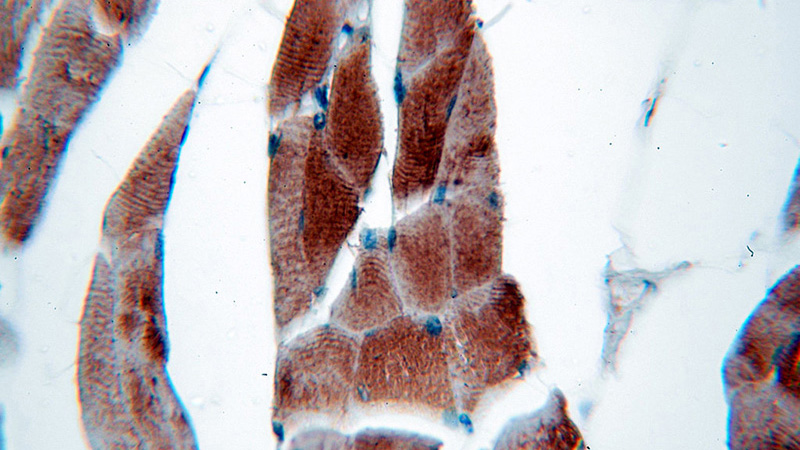

Immunohistochemical of paraffin-embedded human skeletal muscle using Catalog No:113089(NEB-Specific antibody) at dilution of 1:50 (under 40x lens)